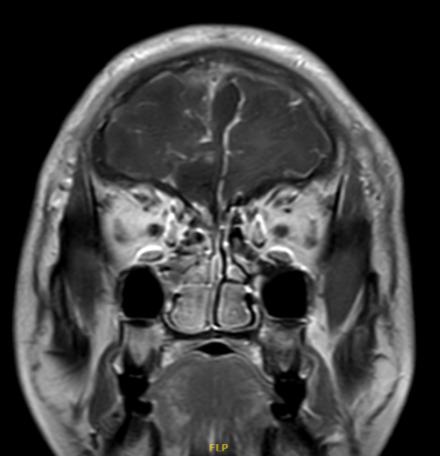

有了术前的精准评估和模拟测试,范学政主任、易剑波医生团队只用了4个小时就将刘先生的肿瘤全切,并在伤口处做了美容缝合,无需拆线,能让伤口更加隐形。

术后病理及免疫组化结果提示:刘先生脑中的瘤子是过渡型脑膜瘤(WHO I级)。幸运的是,过渡型属于良性,生长缓慢,手术切除干净后,一般不会复发。

手术后

肿瘤被切除